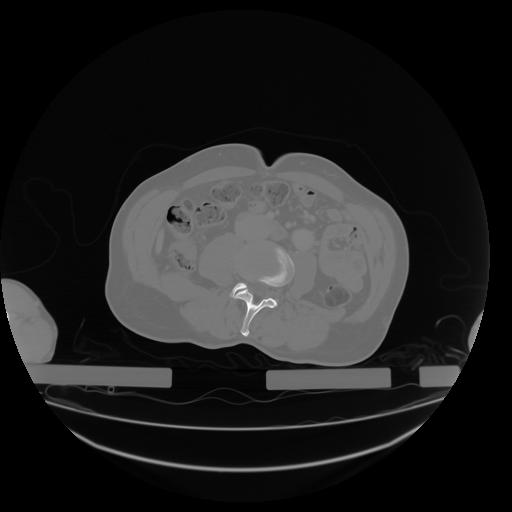

27 CUERPO,CE,Axial,3.0,CUERPO,,